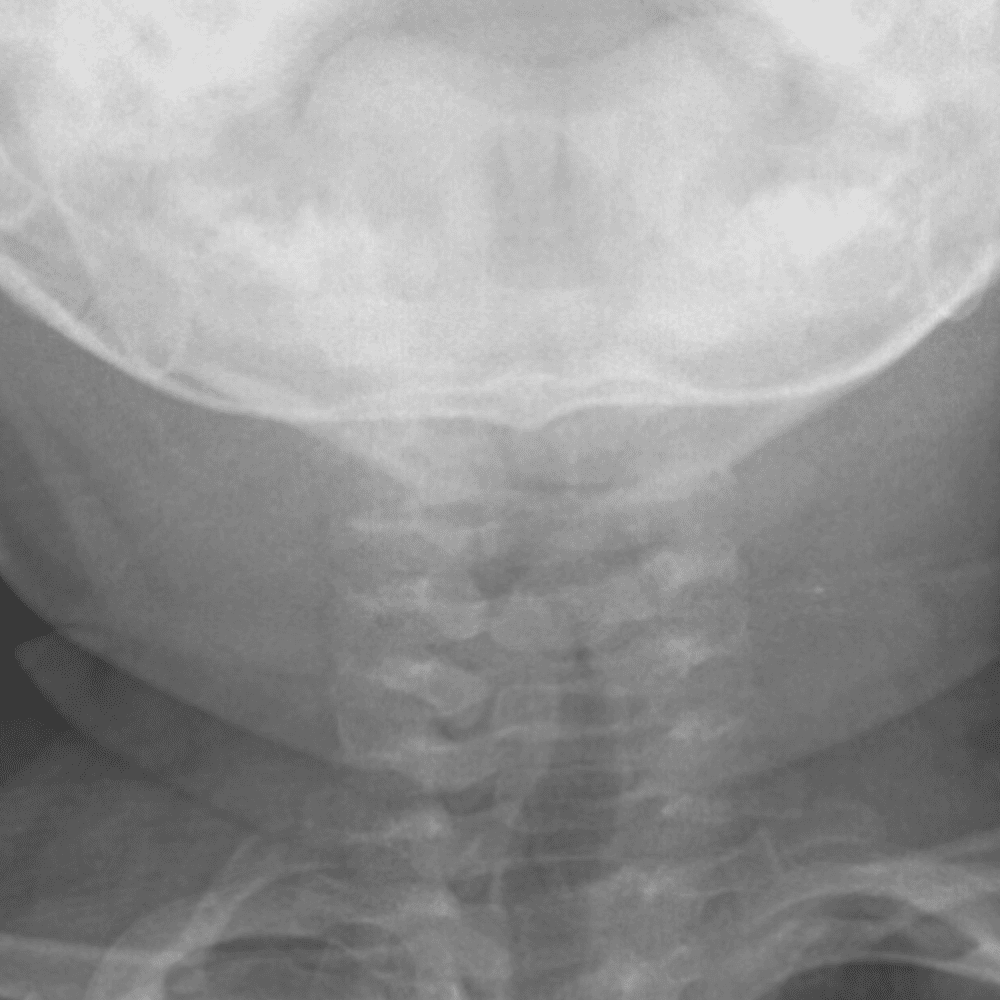

Peds Chest

Practice

Simulates call by including subtle or difficult cases and some normals.

50 cases